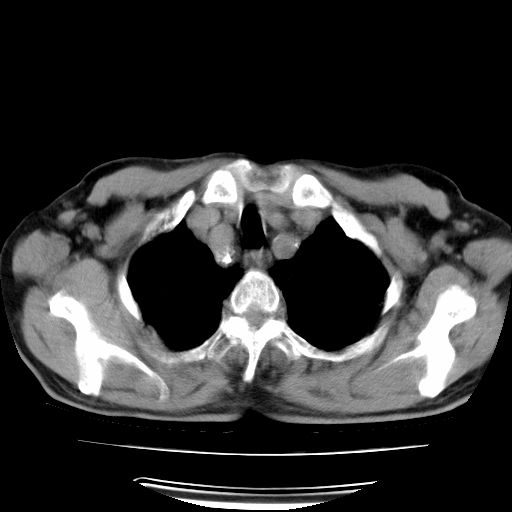

男,71岁,咳嗽,气喘10年,再发并咯血.胸片见气胸

考虑  左肺中心型肺癌伴阻塞性肺炎,肺不张,纵膈淋巴结肿大。慢支炎,肺气肿,左侧气胸肺压缩5%

左侧中央型肺癌伴纵膈淋巴结转移。

左肺中心型肺癌伴阻塞性肺炎,肺不张,纵膈淋巴结肿大

1)考虑左肺中心型肺癌伴阻塞性肺炎、左肺下叶肺不张、左侧肺气肿,纵膈淋巴结转移。2)左侧气胸(肺组织压缩约5%)。

左肺中心型肺癌伴阻塞性肺不张、肺气肿 。

1)考虑左肺中心型肺癌伴阻塞性肺炎、左肺下叶肺不张、左侧肺气肿,纵膈淋巴结转移。2)左侧气胸。